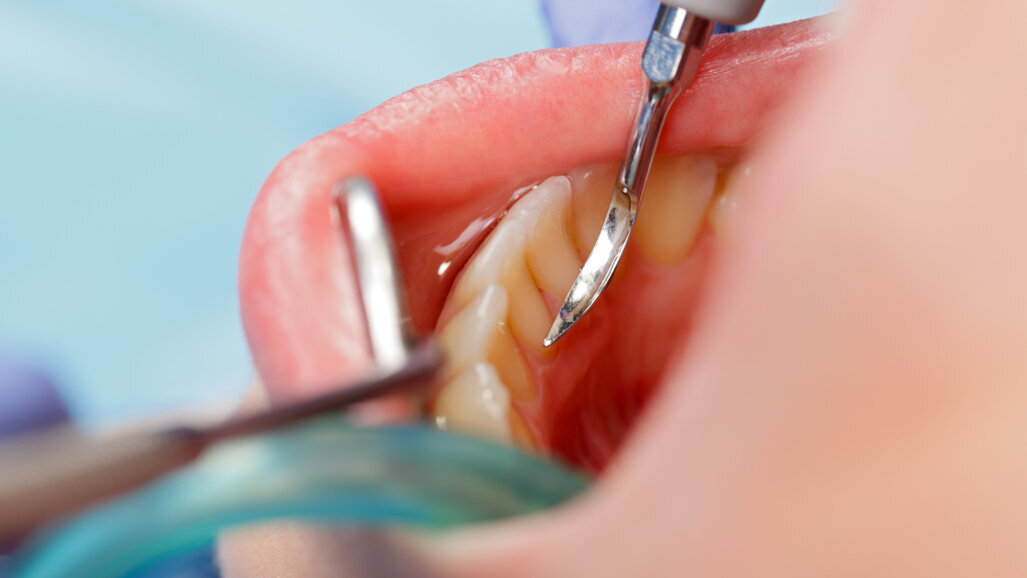

La carie dentale è un dilemma secolare che continua a rappresentare una minaccia per la nostra salute orale e generale. Secondo l'Organizzazione Mondiale della Sanità, circa 2,3 miliardi di persone soffrono di carie dentali nei denti permanenti e più di 530 milioni di bambini soffrono di carie dentali nei denti primari a livello globale. L'Organizzazione ha anche osservato che la prevalenza della malattia orale continua ad aumentare nella maggior parte dei paesi a basso e medio reddito, dove la popolazione si sta spostando sempre più verso le aree urbane e sta vivendo cambiamenti nelle condizioni di vita.

Parlando dell'importanza dei risultati, Qian ha spiegato che lo studio potrebbe contribuire notevolmente alla prevenzione della carie dentale. Ha osservato: «I batteri riparati in un biofilm nella placca dentale possono scatenare grandi quantità di acido che attaccano lo smalto dei denti. Se possiamo impedire ai batteri che formano biofilm di produrre le molecole pertinenti, possiamo prevenire la formazione di placca dentale».